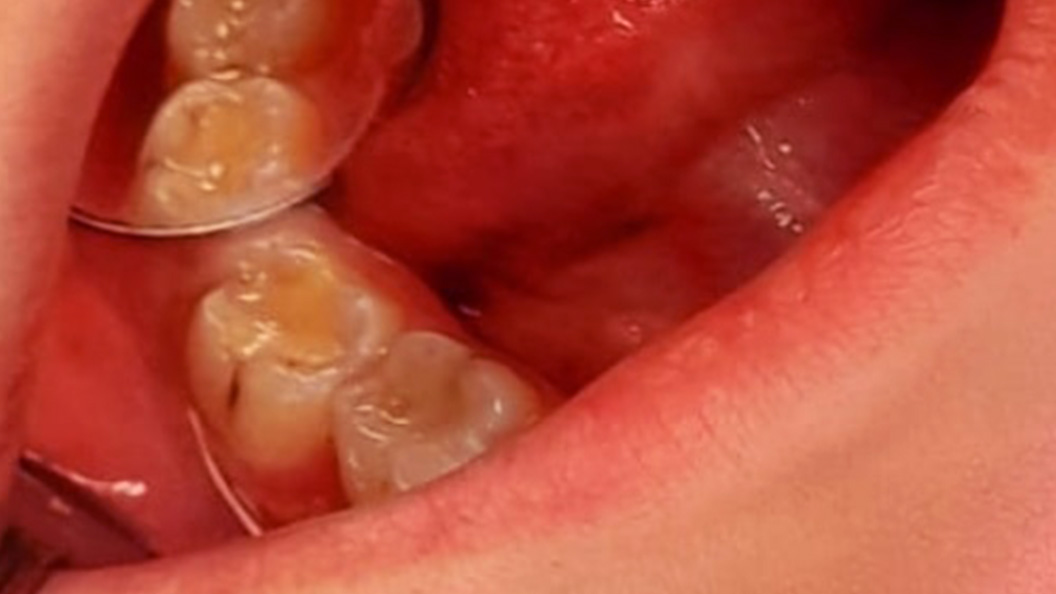

До и после лечения

Пациентка обратилась в «Стоматологию Комфорта» с жалобами на обильный зубной налёт обеих челюстей и кровоточивость дёсен при чистке зубов. Врач диагностировал хронический генерализованный катаральный гингивит и назначил профессиональную гигиену полости рта с помощью ультразвука. В завершении процедуры проведена чистка системой Air Flow и полировка зубов.

Катаральный гингивит возникает чаще всего из-за недостаточной гигиены полости рта и нерегулярных визитов к стоматологу. Заболевание проявляется в виде обильного зубного налёта, покраснения и кровоточивости дёсен, жжения и регулярных болей. В качестве лечения назначают профессиональную комплексную гигиену полости рта. Для профилактики эту процедуру необходимо повторять 1-2 раза в год.

Этапы лечения:

- удаление зубного камня и твёрдых отложений с помощью ультразвука;

- чистка зубов системой Air Flow;

- полировка эмали пастой «Detartrine»;

- медикаментозная обработка десны.